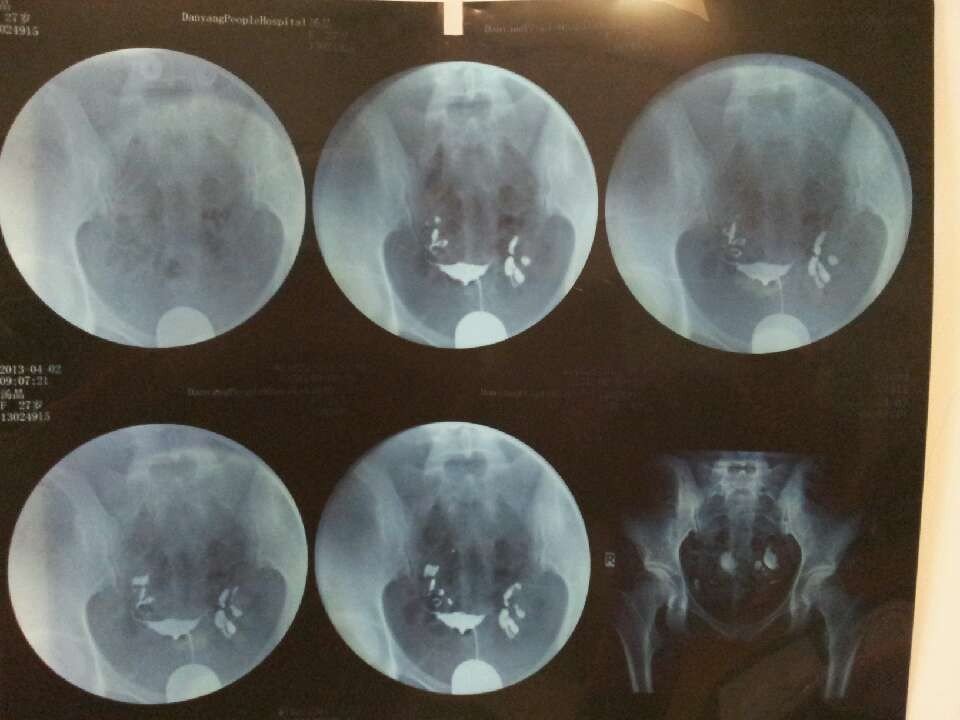

输卵管通畅呈迂曲柔软条形状,伞端显影无殊,24小时后,造影剂在盆腔内弥散不良!

请问有什么治疗办法吗?医生说是腹腔镜半年后不孕会更加严重!还有别的办法解决嘛?